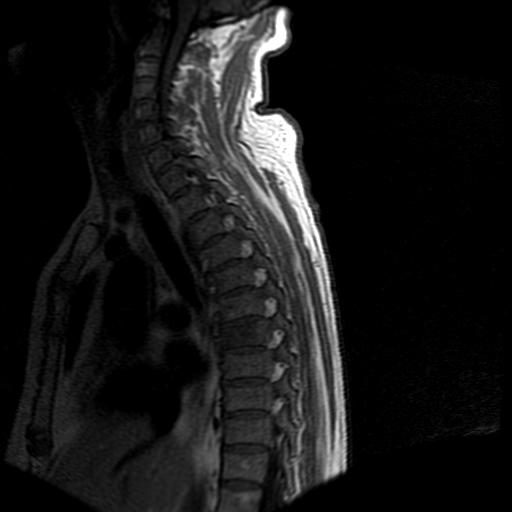

68岁男性,胸部疼痛,不适。

t7椎体前1/3信号略减低,椎体上下面凹陷,相应脊髓几周边软组织信号未见改变。考虑:椎体退变。

胸7椎体楔状变形及信号异常,附件未见明显异常信号.椎间隙正常.未见软组织块影.考虑骨质疏松所致压缩性骨折可能大.

胸7椎体楔状变形及信号异常[t1t2 均为低信号],附件未见明显异常信号.椎间隙正常.未见软组织块影.考虑陈旧性压缩性骨折伴退变。

首先需除外单发成骨性转移瘤可能。

转移瘤也不能排除